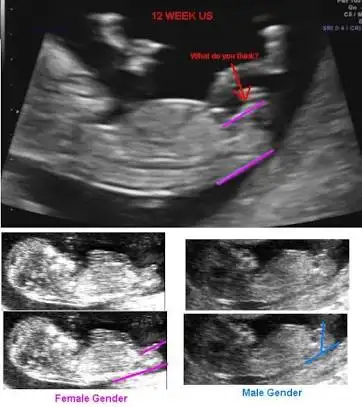

Bu fotoğrafta çok güzel açıklamış female dediği kız da olan çıkıntı sırtına paralel

Male dediği erkekte olan çıkıntı dik açılı yukarı bakıyor